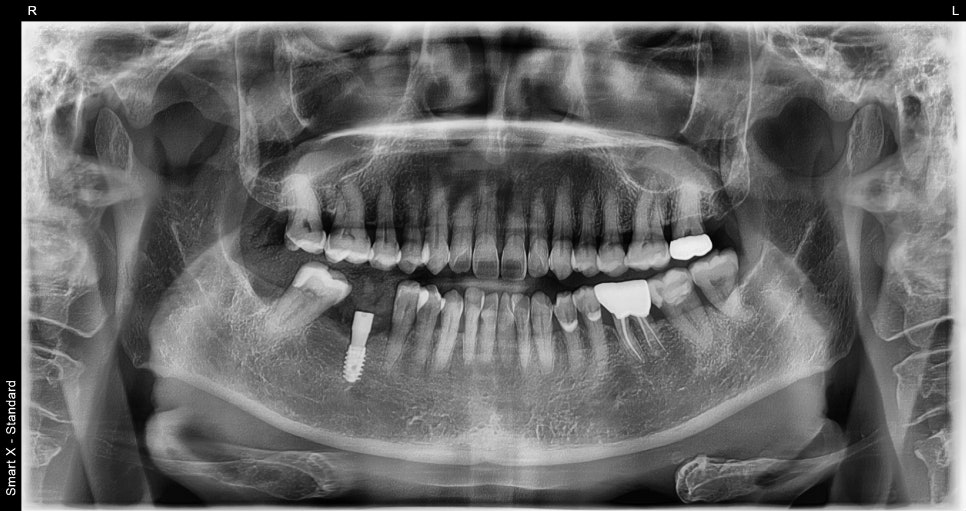

X-ray immediately after surgery

Changes after treatment

✔️ Complete recovery of chewing function

✔️ Reduced burden on the opposite molar

✔️ Prevention of surrounding teeth from tilting

✔️ Normalization of occlusal balance